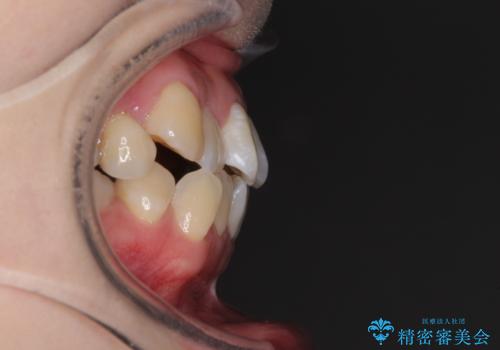

- 前歯がデコボコした上に口元が閉じにくいことを気にして来院された患者様です。

IPR(歯と歯の間を削る)と側方拡大では口の閉じにくさは改善できそうになく、一方で抜歯矯正を行うほどの突出感は認められませんでした。

親知らずを全て抜去し、歯列全体を後方に移動させることで口元の閉じにくさいを改善していくこととしました。